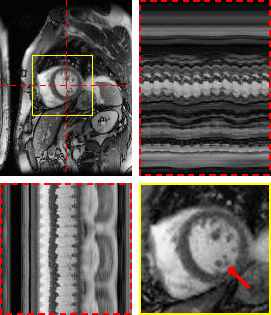

Refer to caption

(a) M-DIP

(b) LR-DIP

(c) L+S

Figure 5: Exemplary free-breathing single-shot LGE reconstructions. Each sub-figure illustrates one frame, temporal profiles, and a close-up of the heart. Red arrows show details that are better visible in M-DIP compared to LR-DIP.

Table 3: Mean scoring results for the in-vivo studies. p𝑝pitalic_p-values of Student’s t-tests with respect to M-DIP are given, where (ns) indicates p>0.05𝑝0.05p>0.05italic_p > 0.05, * indicates p0.05𝑝0.05p\leq 0.05italic_p ≤ 0.05, ** indicates p0.01𝑝0.01p\leq 0.01italic_p ≤ 0.01, and *** indicates p0.001𝑝0.001p\leq 0.001italic_p ≤ 0.001. The best value in each column is written in boldface.

In a further in-vivo study, we applied M-DIP to free-breathing single-shot LGE data, thus demonstrating our method’s suitability for dynamic applications beyond cine imaging. The clarity of myocardial features was rated highest in the M-DIP reconstructions, with a substantial performance gap over LR-DIP and L+S. Similar to real-time cine, LR-DIP reconstructions are blurred, while L+S reconstructions exhibit high levels of noise.